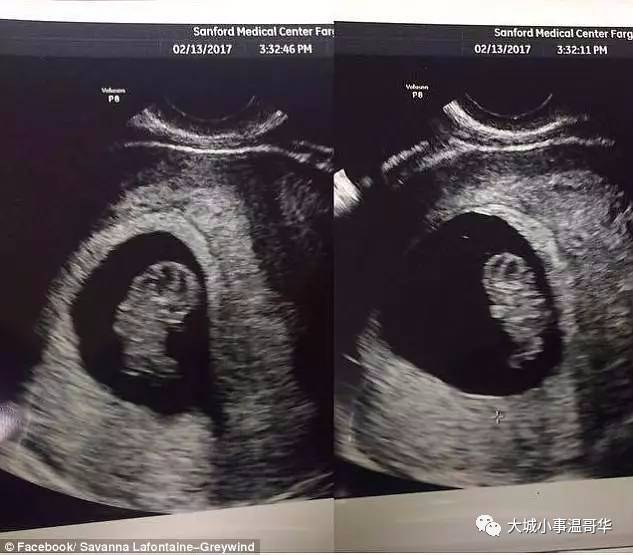

经调查,这名女尸就是22岁的女子Savanna Greywind。

Savanna Greywind

直到8月25日,警方在女邻居家发现了一名只出生了2天的新生女婴

警方通过DNA比对确认了这个婴儿

正是Savanna死前腹中的婴儿!

幸好新生女婴体健康,现在正在医院接受照顾。